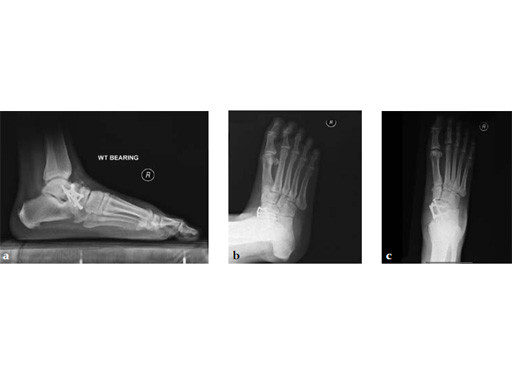

Case 4: First TMT fusion plate

A 60-year-old woman with pes plano abductovalgus (flatfoot deformity).

Case provided by Andrew Sands, New York, New York, USA

The patient was treated by headless compression screw 6.5 tuber osteotomy, TMT plantarflexing osteotomy, and first TMT fusion a plate.